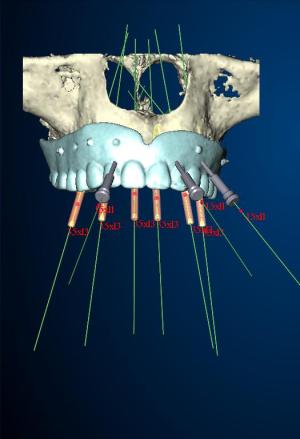

הושק מכשיר הדמייה חדיש בתלת מימד CT, לרווחת המטופלים ולשיפור הטיפול

המרכז הרב תחומי לרפואת שיניים ולאסתטיקת הפה בניהולו של ד"ר יורם רוזן השיק לאחרונה מכשיר הדמייה מתקדם בתלת מימד (CT). המכשיר החדש מתוצרת GENDEX (GX cb-500), מהווה מהפכה של ממש בשגרת העבודה של המרכז הרב תחומי, שכן הוא מעניק לצוות הרפואי של המרכז אפשרות לאבחונים מהירים מאוד ומדוייקים מאוד, המאפשרים קבלת החלטות רפואית בזמן אמת. […]

NOBEL GUIDE – ההייטק של הרפואה הדנטלית

NobelGuide היא תוכנה מיוחדת לביצוע השתלת שיניים בשיטת השתלה מתקדמת. השיטה פותחה במעבדות Nobel Biocare – החברה הדנטלית הגדולה והוותיקה ביותר בעולם. השתלת שיניים באמצעות NobelGuide מבוססת על הדמיה בתלת מימד בסיוע C.T.. הדמיה מיוחדת זו משפרת את הדיוק של השתלת שיניים ומאפשרת לרופא השיניים לתכנן מראש את מהלך ההשתלה ולבצע אותה במהירות, בדייקונות וביעילות. […]

העמסה מיידית (Immediate function) על לסת חסרת שיניים באמצעות ארבעה שתלים

אחד המושגים שמשנים בשנים האחרונות את פני השיקום הדנטאלי הוא "העמסה מיידית" Immetidate implant function, שיטת השתלה שהפכה למתודת טיפול מקובלת ונפוצה יותר ויותר, למטרות שיקום קבוע של מערכות שיניים שלמות, במקרים בהם חסרות כל השיניים בלסת. הפרוטוקול המקורי, עם הניסיון המצטבר הרב ביותר בעולם בתחום זה, הוא הפרוטוקול של ד"ר פאולו מאלו, אותו אימצתי […]